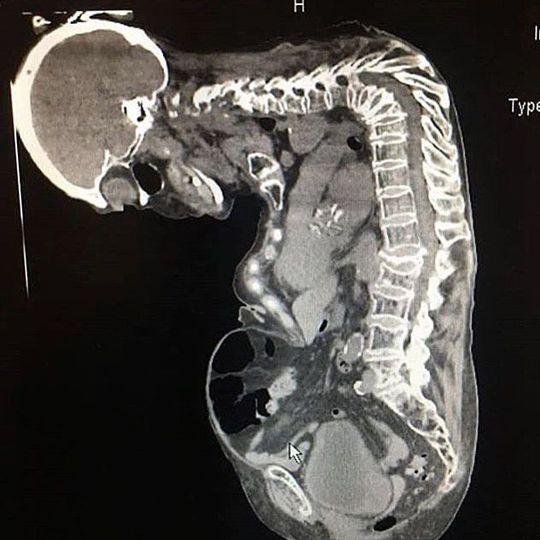

Gibbus deformity is a short-segment structural thoracolumbar kyphosis resulting in sharp angulation. The anterior collapse of one or more vertebral bodies resulting in kyphosis of a very sharp angle, as seen here. It is typically found in the upper lumbar and lower thoracic vertebrae, where one or more adjacent vertebrae become wedged. It often develops in young children as a result of spinal tuberculosis and is the result of collapse of vertebral bodies due to spinal infection and osteomyelitis. This can in turn lead to spinal cord compression causing paraplegia, as well as myelopathy, if untreated. In addition to tuberculosis, other possible causes of gibbus deformity include pathological diseases, hereditary and congenital conditions, and physical trauma to the spine that results in injury. Gibbus deformity may result from the sail vertebrae associated with cretinism (the childhood form of hypothyroidism), mucopolysaccharidosis (MPS), and certain congenital syndromes, including achondroplasia. Because most children with MPS I (Hurler Syndrome) also exhibit symptoms of a gibbus deformity, the latter can possibly be used to identify the former. Gibbus deformity is included in a subset of structural kyphosis that is distinguished by a higher-degree angle in the spinal curve that is specific to these forms of kyphosis. Other conditions within this subset include Pott’s disease and Scheuermann kyphosis, but gibbus deformity is marked by an especially sharp angle. Viewed from behind, the resulting hunchback is more easily seen when bending forward. A kyphosis of >70° can be an indication of the need for surgery and these surgeries can be necessary for children as young as two years old, with a reported average of 8 years of age. Patients complain of mid-back pain and stiffness. Treatment for Gibbus deformity, caused by infectious sources, requires both antibiotics to treat osteomyelitis as well as surgical correction which usually involve corpectomy, interbody cage placement, and posterior instrumentation and fusion.